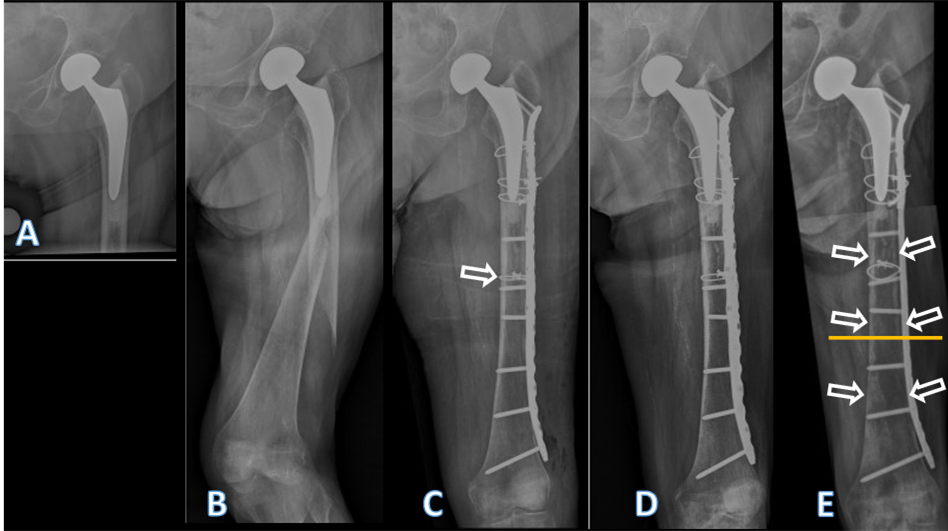

An 80-year-old female had been treated with a cemented HHA (AMIStem-C, Medacta, Castel San Pietro, Switzerland) for a low-energy femoral neck fracture (Fig. 1a). Two years later, the now 82-year-old patient tripped and fell again, suffering a PPF of the femur (Figs. 1b and 2).

Figure 1: Conventional anteroposterior radiographs of the left hip, respectively, the left fe-mur of the patient described. In (a) after cemented hemiarthroplasty, performed due to a femoral neck fracture, at an age of 80 years. In (b) periprosthetic spiral fracture of the fem-oral diaphysis, 2 years postoperatively, following a low-energy fall. In (c) after internal fix-ation of the femur. The fracture was first reduced with a cerclage (arrow), then a lateral neu-tralization plate was applied, fixated proximally with further cerclages and distally with screws. In (d) follow-up 4 months after internal fixation. Note that no callus formation is visible, indicative of absolute stability. In (e) follow-up 4 years after internal fixation. Note the atrophy of the cortical bone, both medially and laterally, but particularly under the plate (arrows). There were no signs of loosening of the stem, nor of the cement mantle. The yel-low line marks the level of the cross-section from Figs. 4 and 5.

As the treating team considered the stem to be stable, with a fracture evaluated as being located distally to the area of fixation (Unified Classification System [UCS] Type C) [17], plate fixation was chosen. Open reduction and internal fixation of the fracture was performed through a subvastus approach, with reduction and fixation by a cable cerclage (Cable System 1.7 mm, DePuy Synthes, Zuchwil, Switzerland) and application of a lateral neutralization plate (non-contact bridging [NCB] Periprosthetic Femur Plate System 18 hole, Zimmer Biomet, Zug, Switzerland), fixated distally with screws and along the level of the stem with further cable cerclages (Cable System 1.7 mm). Postoperatively, the patient was mobilized in a wheelchair, as full weight-bearing was not recommended and as it was not possible to implement partial weight-bearing. Wound healing was uneventful. The radiological follow-up after 8 weeks showed intact material without evidence of loosening (Fig. 1c). Mobilization under full weight-bearing with support by physical therapy was then attempted. Four months postoperatively, the radiological follow-up showed a general atrophy of the cortical bone, which was accentuated at the lateral cortex, underneath the plate (Fig. 1d). Mobilization was hampered due to thigh pain, which had been interpreted to be caused by muscle atrophy. Thus, further physical therapy was recommended. As the impaired mobility caused difficulties attending consultation at the hospital, no further follow-up visits were planned. Due to increasing thigh pain, the patient was readdressed for evaluation by her general practitioner 4 years after the operative treatment of the PPF. Not having been mobilized outside a wheelchair in the meantime, the patient showed bilateral hip and knee flexion contractures. Consequently, she was unable to stand, disregarding the issue of thigh pain. Radiologically, there was now pronounced atrophy of the cortical bone of the femur, particularly of the lateral cortex under the plate (Fig. 1e). An infection was considered unlikely, as there was no pain at rest, as the soft tissues were inconspicuous, as the fracture had healed, and as there were no general symptoms. A single-photon emission computed tomography (CT) showed avascular areas of cortical bone underneath the plate (Fig. 3). The CT better illustrated a general atrophy of the femur with thinning of the bone cortex in comparison to the contralateral femur (Fig. 4 and 5). There was, however, no sign of loosening of the stem. Considering comorbidities, very limited potential for recovery, and the patients’ desire for no more surgery, the option of a revision was rejected, accepting the present situation. The patient died 7 months later.